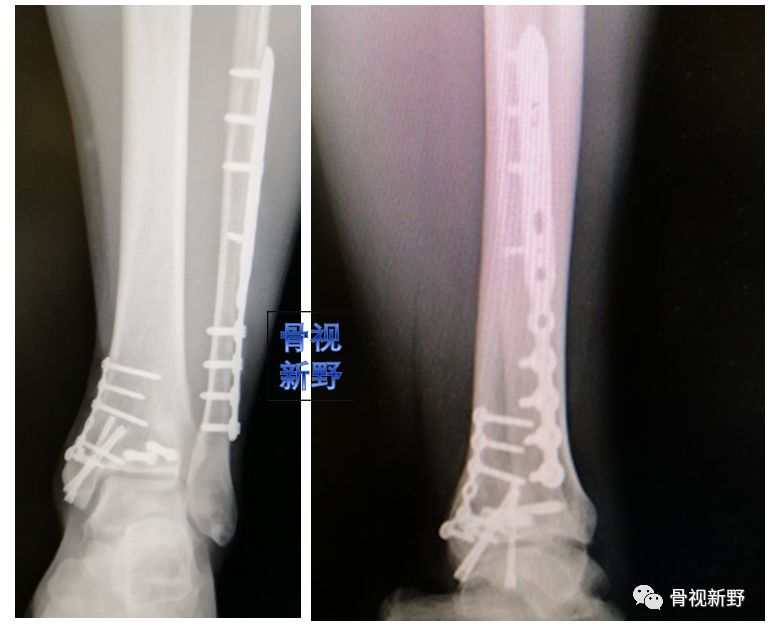

后踝/后Pilon骨折的buttress固定

后踝骨折和后Pilon骨折的界限一直不是很清楚。一般认为旋转性损伤机制、骨折块小、没有压缩的胫骨远端后方骨折属于后踝骨折,而跖屈损伤机制、骨块大、有压缩者往往属于后Pilon骨折。不稳定、较大骨块的后踝骨折及后Pilon骨折用空心钉固定有可能不能很好地中和向上的剪力,可选择butress钢板作防滑固定,以对抗垂直剪力。

锁定重建板作buttress钢板

锁定“T”型钢板作buttress钢板

3.5mm干骺端锁定钢板作buttress钢板